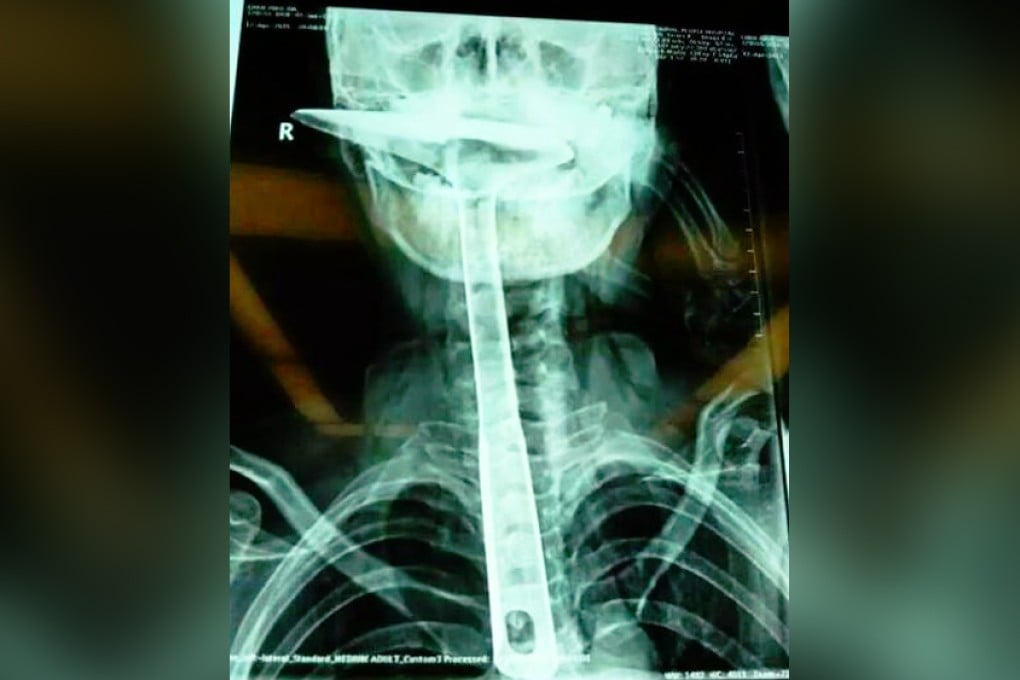

A woman in southern China was almost killed when she tried to clear her throat by forcing the handle of a 30cm-long kitchen spatula down her mouth, according to a newspaper report.

She first tried her fingers and then chopsticks to clear her throat and finally forced the handle of the spatula down her mouth.

Doctors have carried out two operations on the housewife and removed most of her oesophagus, according to the report.